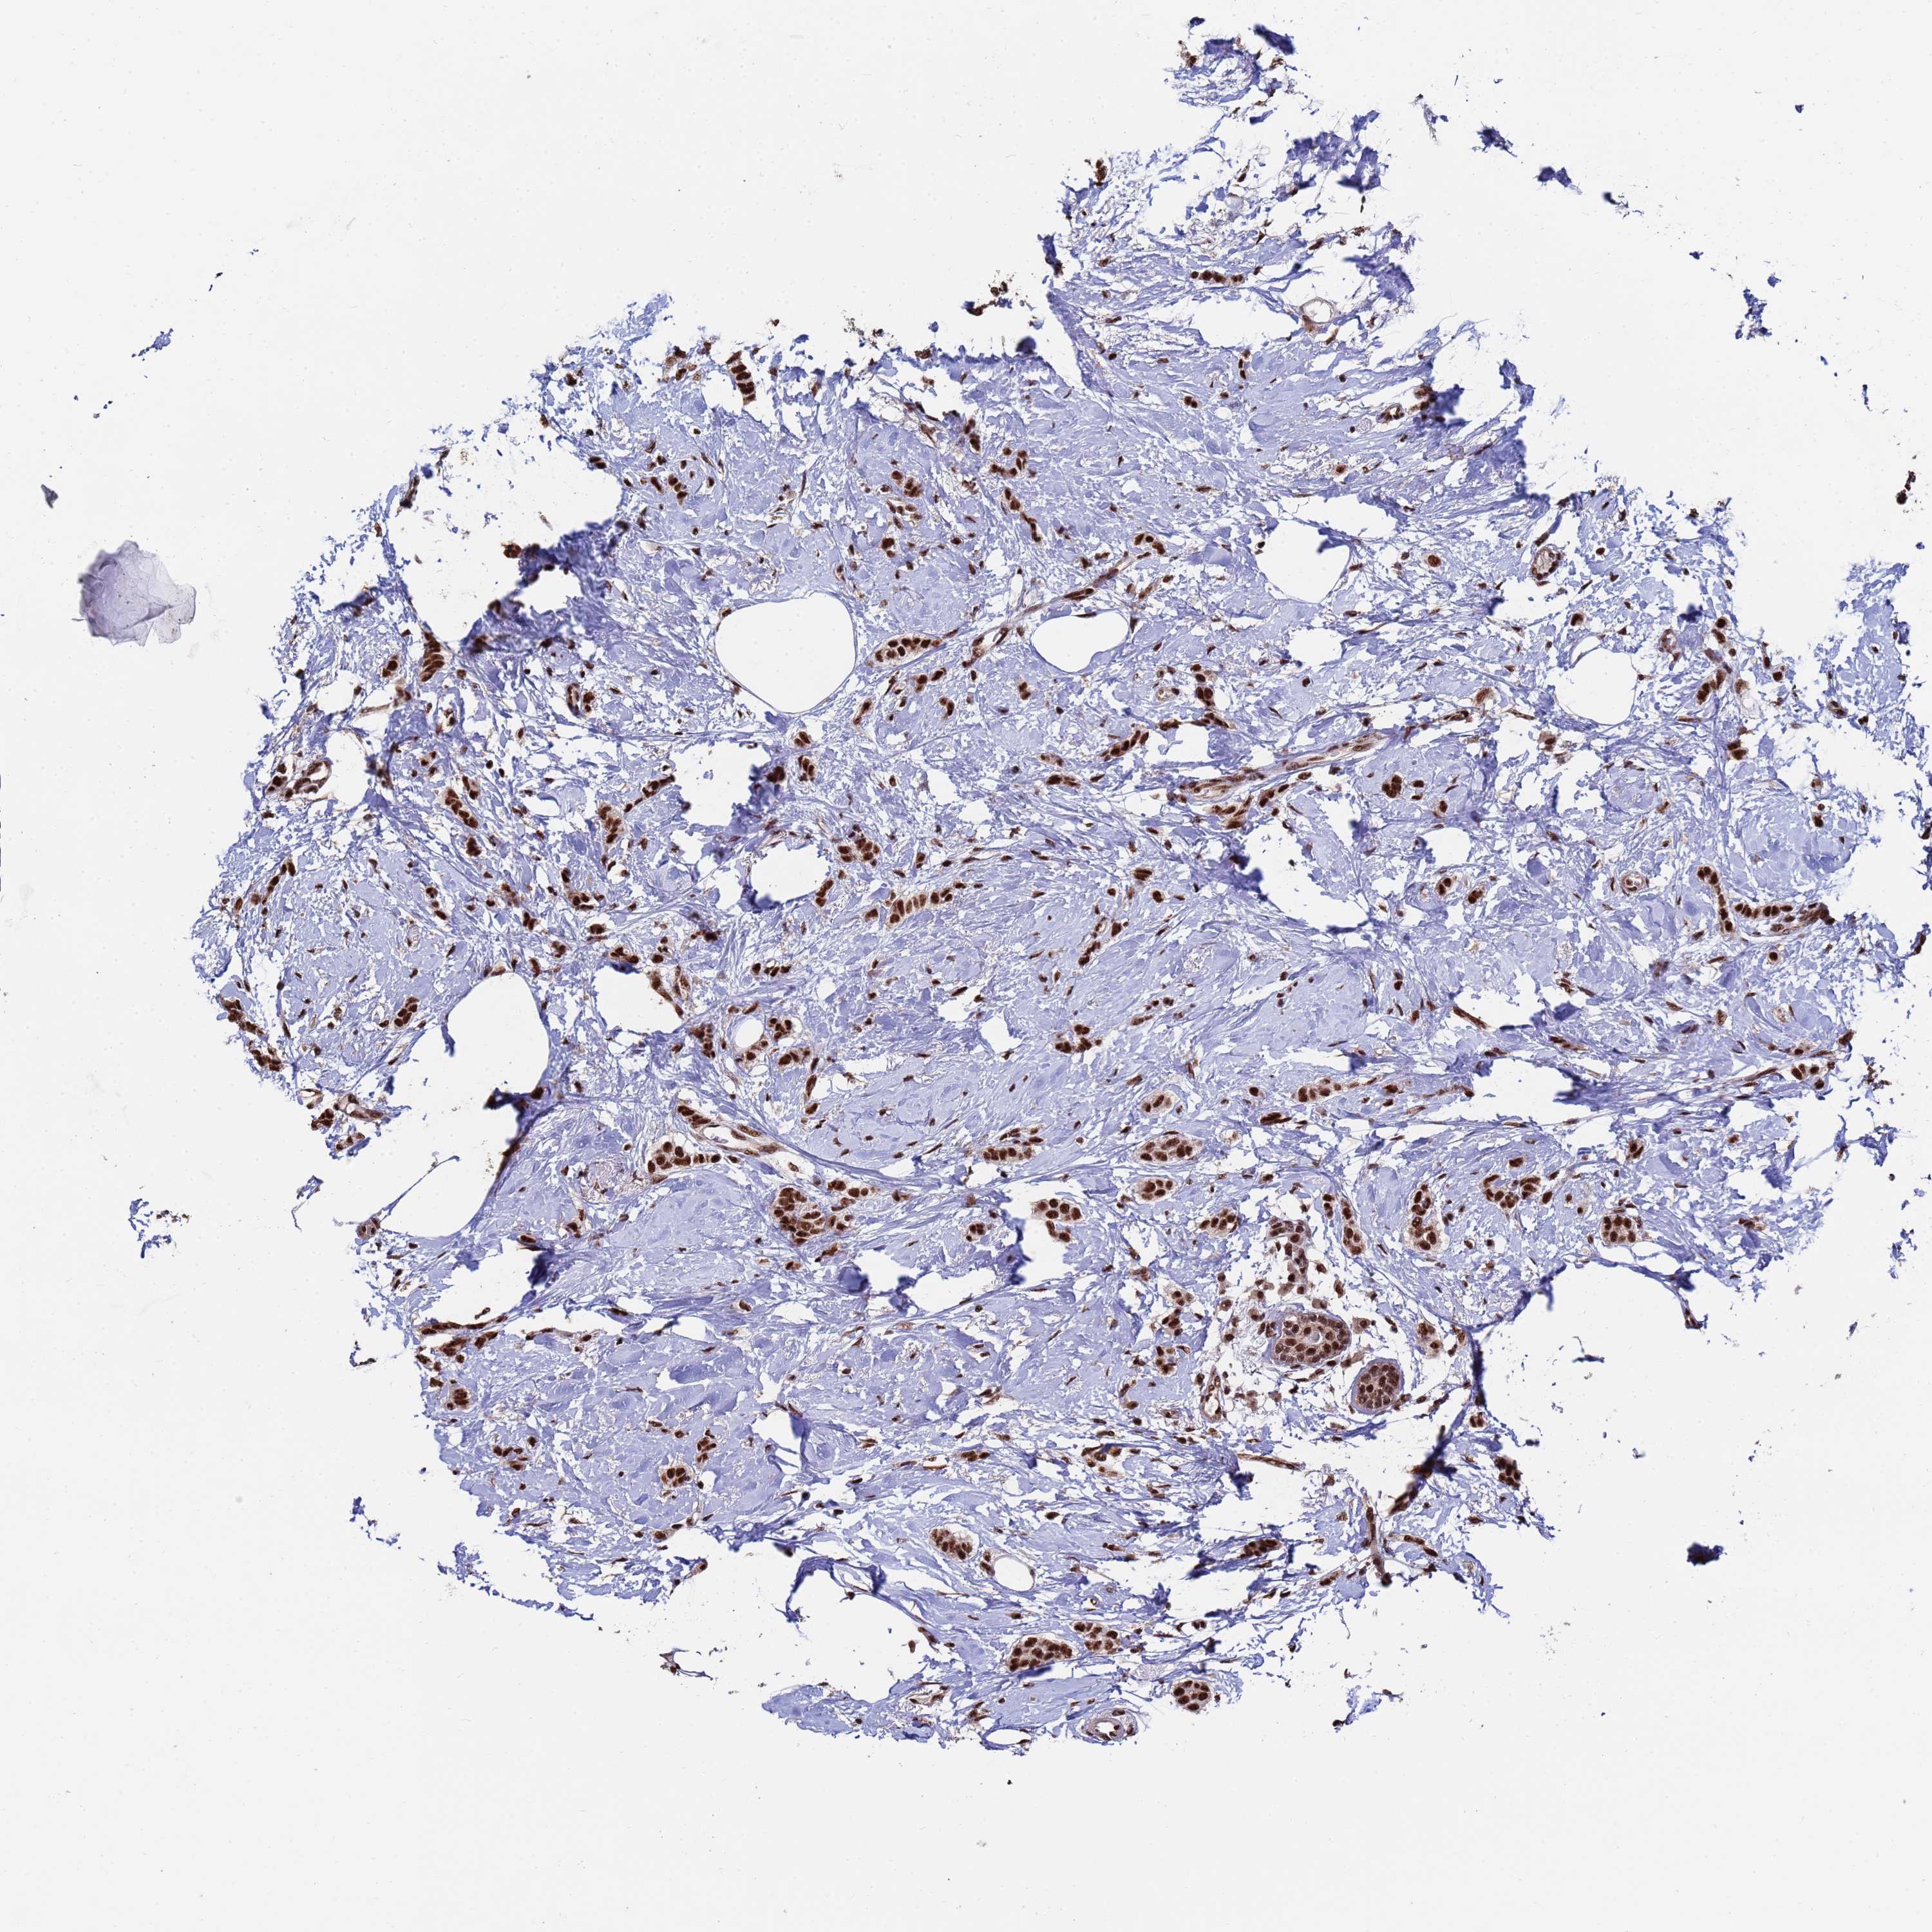

CANCER BREAST CANCER Show tissue menu

BRCA TCGA BRCA VALIDATION PROTEIN EXPRESSION